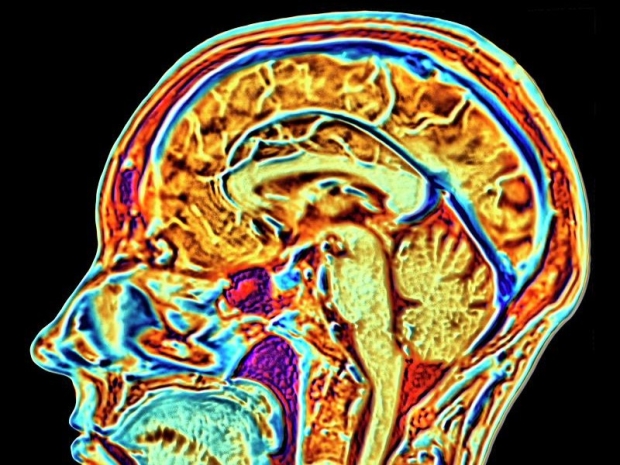

The firm aims to link human brains to computers and wants to help sort out tricky brain problems.

This lets them start the six-year study where a robot is used to stick 64 bendy threads, thinner than a human hair, onto a part of the brain that controls movement.

The firm says that these threads let its trial implant - powered by a battery that can be charged without wires - record and send brain signals to an app that works out how the person wants to move.